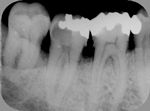

◆ドックベストセメント療法

削らないむし歯治療で注目されているセメントです。

セメントの殺菌効果により、通常では神経を抜くであろう深いむし歯治療においても有効です。

ドックスベストセメントを使用することで歯の神経保存率が高まります。

この治療は自費治療となります。

ドックスベストセメント

~初診~

~歯髄に近い深い虫歯~

~ドックベストセメント処置~

~グラスアイオノマー仮封~

~CR充填~

◆根管治療